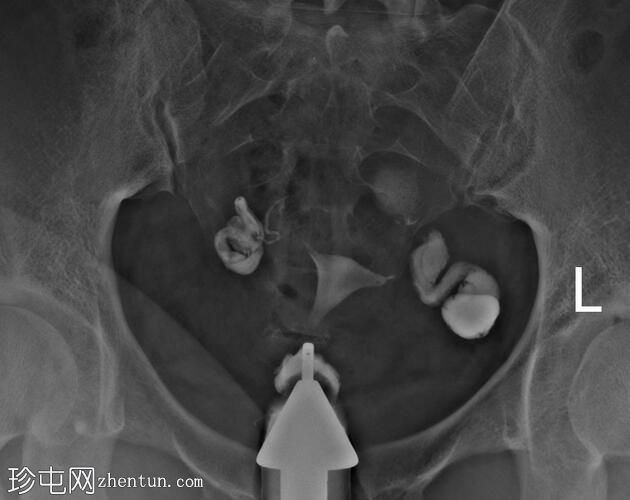

子宫体位于盆腔中线,形态及轮廓正常。

宫颈管长度正常,黏膜表面扩张良好。

右侧输卵管扩张并充满液体,无腹膜溢出,提示输卵管积水及输卵管阻塞。

左侧输卵管亦扩张并充满液体,伴有造影剂残留及少量溢出,提示输卵管积水及输卵管阻塞。

此外,左侧盆腔内,位于输卵管上内侧,可见大量分隔的造影剂积聚,并伴有盆腔输卵管周围粘连。

子宫输卵管造影结果符合双侧输卵管阻塞和输卵管积水,左侧输卵管周围可见分隔的造影剂渗漏。